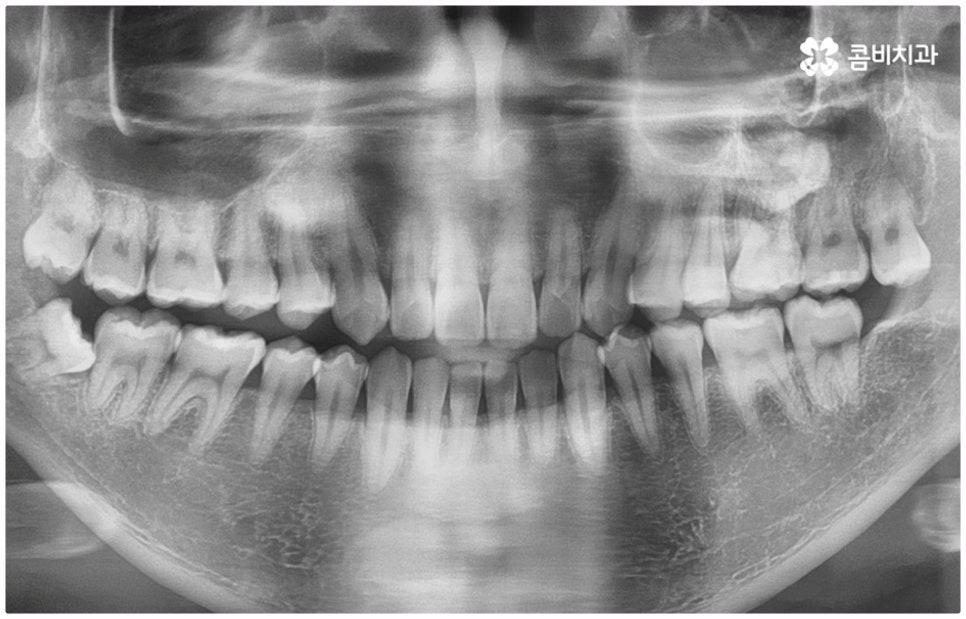

위아래 치아의 교합이 잘 맞지 않는 부정교합을 가지고 있으면 외적인 자신감이 떨어질 뿐 아니라 기능적으로 잘 씹지 못하고 말을 할 때도 발음이 부정확해지는 문제가 생길 수 있기 때문에 교정 치료 등으로 바로잡아 줄 필요가 있어요. 부정교합은 1급, 2급, 3급으로 나눌 수 있는데 오늘은 특히 부정교합 3급 중 절단교합 케이스에 대해 자세하게 알아보려고 하고 있습니다.

부정교합 3급 이란 입을 다물었을 때 아래 어금니가 윗 어금니보다 전방에 위치한 경우를 가리키는 것으로 그 중 절단교합은 이 상태에서 위아래 앞니 끝과 끝이 맞닿는 교합을 의미하는 거예요. 이에 비해 정상적인 교합은 어금니는 똑바로 맞물리고 윗 앞니는 아랫 앞니를 살짝 덮는 정도로 겹쳐지면서 자연스럽게 조금 앞으로 나와 있는 상태를 말하고 있습니다.

물론 교정 치료에 적기가 정해져 있는 것은 아니기 때문에 성인 이후 중장년 환자분들이라도 교정 치료가 불가능하지는 않으며 상황에 따라 비수술적인 방법으로도 얼마든지 불편함을 줄일 수 있는 경우가 있으니 정확하게 진단한 후 각자에게 맞는 교정 계획을 세워 무리하지 않게 치료를 진행하시길 바라고 있어요. 특히 턱관절과 관련된 부분을 개선하기 위해서는 양악 수술 밖에 방법이 없는 것이 아닌가 생각하셨던 분들이라면 먼저 치과에 내원하셔서 검진과 상담부터 진행해 보시면 마음의 부담을 덜 수 있어 좋을 거예요. 부정교합 3급 치열 (절단교합과 일부 반대교합이 병행되어 있음) 을 가지고 있는 성인분도 교정 치료를 통해 훨씬 자연스럽게 개선이 가능할 수 있으며, 관련 기술 개발 및 미니스크류 등 여러 장치의 발전을 통해 예전에는 적용이 어려웠던 케이스들도 이제는 교정 치료의 도움을 받을 수 있습니다.

치료 계획을 세울 때는 3D CT 같은 정밀 검진 기계를 통해 부정 교합의 정도 및 상하악 관계, 잇몸 건강 상태 등을 꼼꼼하게 살펴보고 회복력과 진행 속도에 영향을 주는 연령, 생활 습관, 평소에 앓고 있는 질환은 없는지 등도 모두 고려하여 세밀한 맞춤 플랜을 세워야 하며 같은 주걱턱 증상이라도 심각한 정도와 턱의 모양에 따라 교정 방법이 달라질 수 있는 만큼 다양한 케이스를 다뤄본 임상 경험을 바탕으로 높은 기술력을 가지고 있는 의료진에게 교정 치료를 받는 것이 굉장히 중요한 포인트라고 할 수 있어요. 정밀 검진 장비 보유 여부, 술자의 뛰어난 숙련도와 함께 체계적인 교정 시스템을 갖추고 사후 관리를 철저하게 해 주는 치과에서 처음부터 끝까지 무리하지 않게 치료를 받는 것도 중요하니 이런 부분도 체크해 보시길 권유드리고 있습니다.

전체 치료 기간은 약 18개월이 소요되었으며,